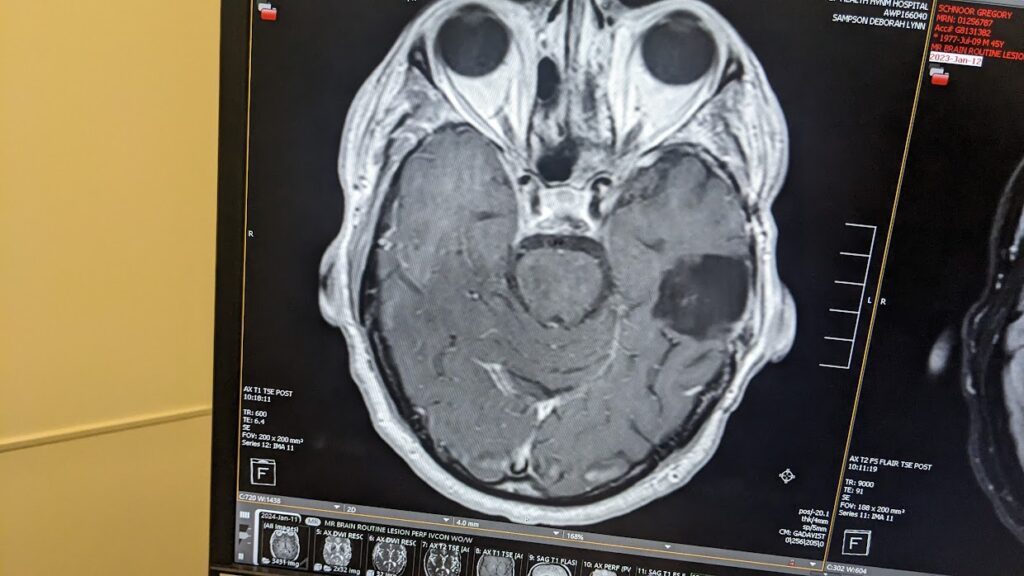

I was all set for the procedure when my ENT (Ear, Nose, and Throat) doctor reviewed the pre-operative scans. The next morning I didn’t get a call with fasting instructions — I got a call telling me my surgery was cancelled. The radiologist had spotted something that didn’t belong: a brain tumor. My ENT immediately referred me for a brain MRI.

After this new diagnosis, I tracked down the scans from that original surgery. When I brought them to my neurosurgeon, the truth came out: the tumor had been there all along — missed for half a decade. While it’s unsettling to know it was growing while I struggled with those “mystery” headaches, I try to focus on the silver lining.